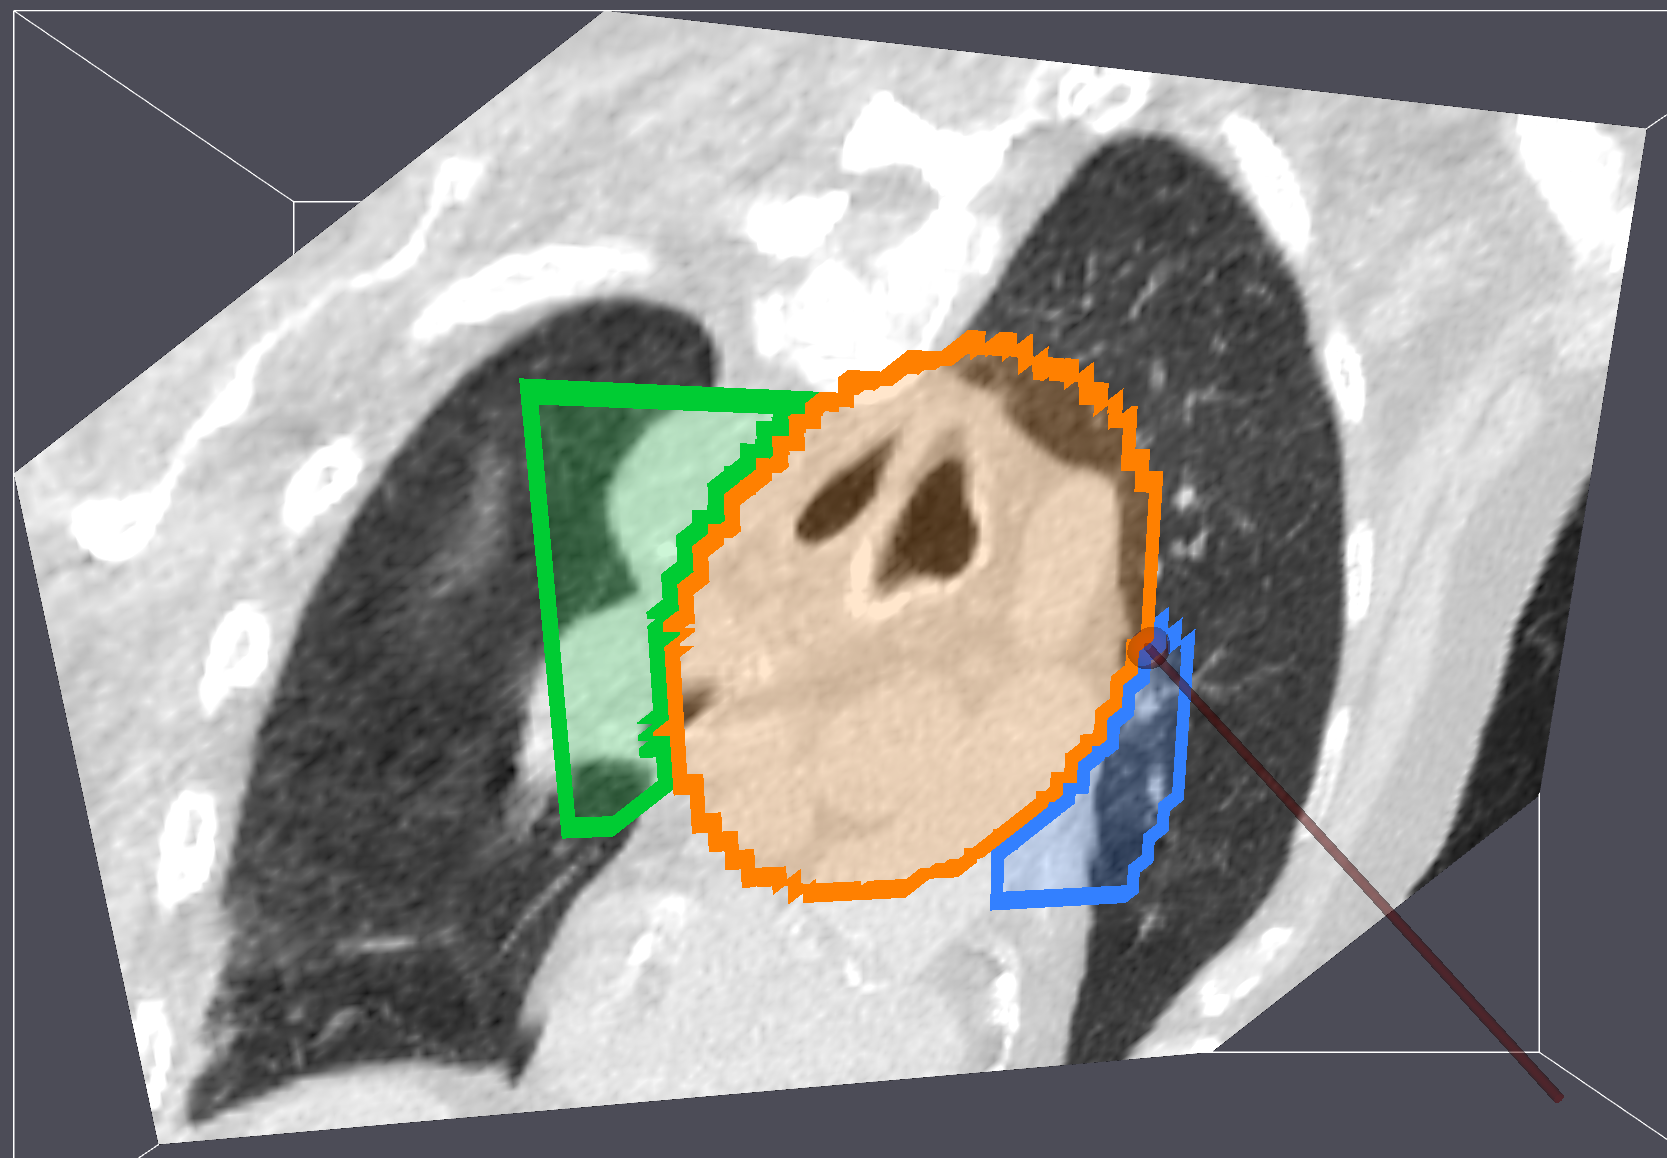

Multi Image Volume Rendering

To support separate background images (MRI, CT) and segmentation images, the VolumeMapper and ImageResliceMapper now takes multiple input volumes. Each input volume gets its own 3D texture (sampler3D), so background and segmentation images can be uploaded independently on the GPU.

Previously, overlaying segmentation labels on a medical image required packing everything into a single multi-component vtkImageData. Adding or removing a labelmap no longer requires re-uploading the base image.

The quality of the rendering has been improved in the process by fixing subtle normal computation bugs that affected lighting and shading quality.

Try out the VolumeMapper example.

Reslice Labelmap Outline Rendering

The ImageResliceMapper renders an oblique 2D slice of a 3D image volume by reslicing it along an arbitrary plane. We added label outline rendering with configurable thickness and opacity in PR #3406

Try out the ImageResliceMapperLabelOutline example.